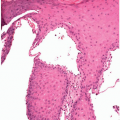

MICROSCOPIC FINDINGS

Acrochordons (fibroepithelial polyp) are composed of a fibrovascular, collagen-rich stroma with a definable stalk that contains prominent thin-walled vessels running parallel to the long axis of the stalk. The polyp is covered with a keratinized epithelial surface that may be thickened, with acanthosis, papillomatosis, and hyperkeratosis, or thinned and atrophic appearing. The epithelium may be folded, with an irregular, undulating surface. The acrochordon may be composed primarily of epithelial or stromal elements, with the larger examples being predominately stromal. The stroma consists of loose bundles of collagen and contains thin-walled vessels. In some cases the stroma is edematous and may be hypocellular. The stromal cells are usually relatively uniform; however, some nuclear pleomorphism may occur and, in rare cases, moderate to marked atypia may be seen. Inflammation is minimal unless there is erosion or ulceration of the epithelial surface. In such cases the inflammation typically involves the superficial subepithelial stroma.